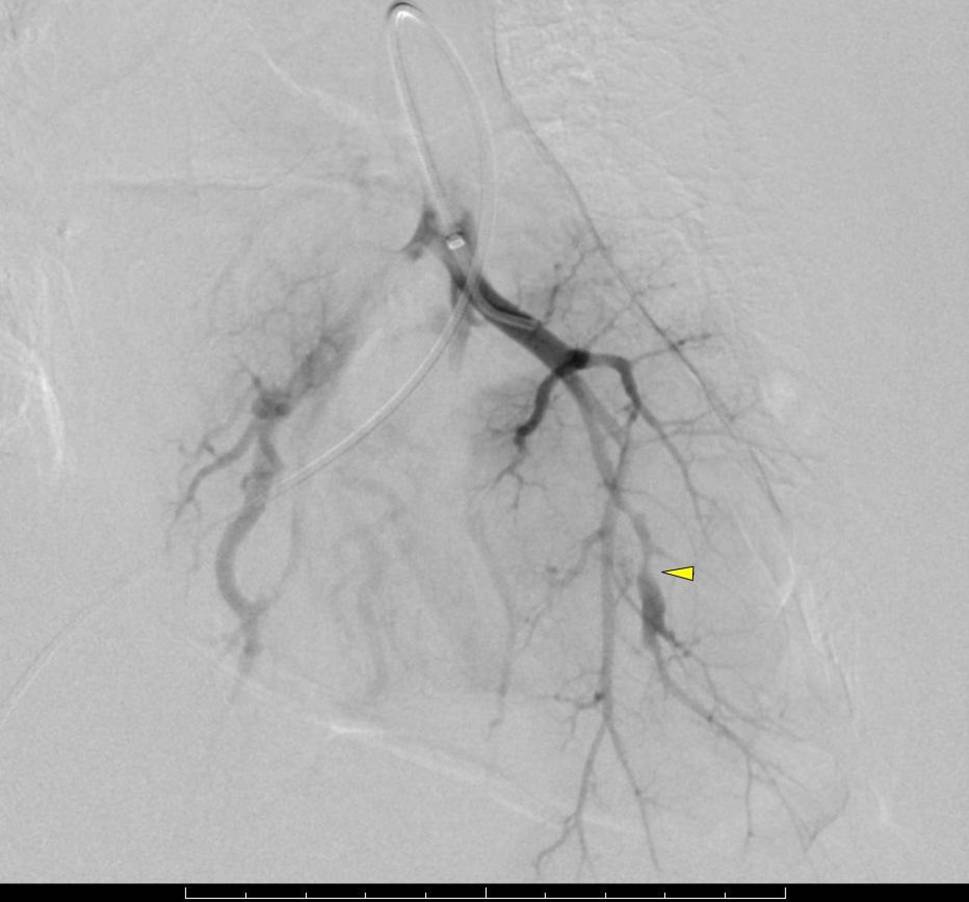

Thoracic CT scan revealed another increase in size of the cysts by an average of 5 mm. A large one in the left lower lobe was filled with liquid and surrounded by dense intrapulmonary opacity, suggesting hemorrhage (Fig. 3). By interventional radiology, the segmental pulmonary arteries 8 and 9 on the left side were identified as the source of the bleeding and were coiled, whereupon hemoptysis subsided (Figs. 4 and 5). The chest tube could be removed uneventfully.

Fig. 4

Angiography of the pulmonary artery shows contrast medium extravasation (arrow)